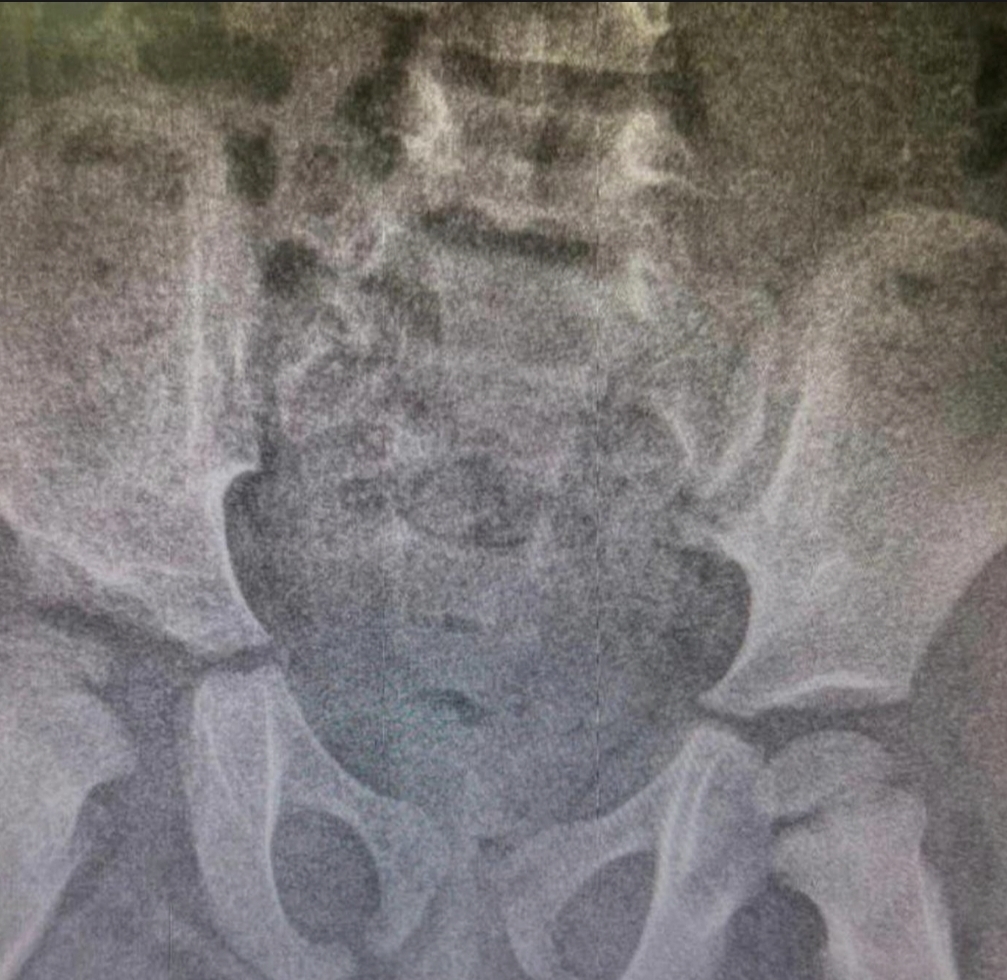

وأوضح قائد الفريق الطبي استشاري وبروفيسور عظام الأطفال الدكتور عمار العمران أن الطفلة البالغة من العمر 4 سنوات خضعت لعمل التقييم اللازم عبر الفحص السريري وعمل الأشعة، وقرر الفريق المعالج بعمل جراحة ترميم وتقويم للمفصل, مشيراً إلى أن الأشعة أوضحت بعد العملية التي استغرقت قرابة 4 ساعات نجاح العملية ورجوع مفصل الورك، وأن الفحوصات الإكلينيكية للمريضة كشفت تحسناً ملحوظاً في مستوى حركة مفصل الورك والأداء الوظيفي بدون ألم.